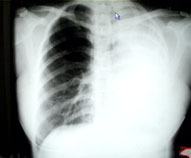

主持人:继续看这段采访。经过确诊女患者小陆已经是左肺全肺不张,这时医生建议她做手术切除左肺。 李强:患者刚到我院时情况确实很严重,从当时的X光片中可以看到患者的左肺已经是完全不张了,而且由于左肺的不张气管被严重的牵拉到左侧,另外从支气管镜片中可以看到整个左主支气管已经完全被结核病灶所闭塞了,因此病人稍微一活动就会觉得呼吸困难。最后完全堵住就会形成肺不张。

主持人:肺不张是一种什么情况? 李强:正常的肺部会有一些气体,由于支气管完全阻塞后肺部的气体完全被吸收了,肺也就丧失了呼吸的功能,所以病人就会感到呼吸的困难。